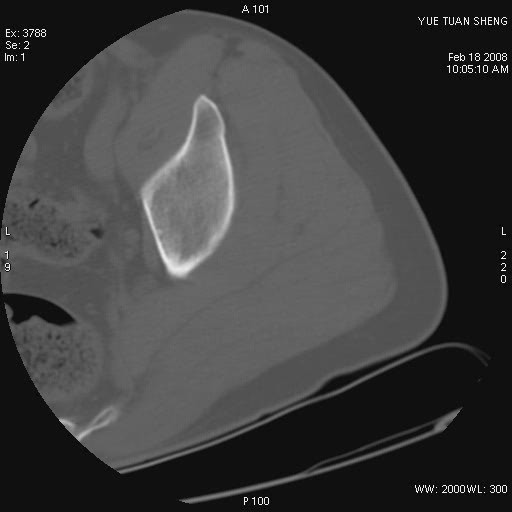

患者,男,56岁,左髋部疼痛1个月,x线:左股骨头高密度影,性质待定,右侧正常。左髋ct如图

左股骨颈区椭圆形磨玻璃样影,边缘明显硬化环环绕,其内见斑点状类钙化高密度影考虑 良性骨病-----骨纤,骨化性纤维瘤,内生软骨瘤。